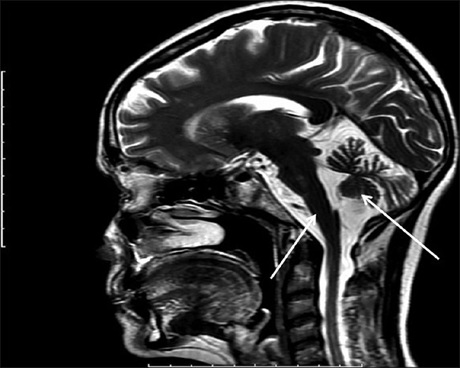

Multiple system atrophy (MSA) is a synucleinopathy, characterized by combined manifestations of cerebellar, parkinsonian, and autonomic features. It is subdivided into two main types-parkinsonian MSA (MSA-P) and cerebellar MSA (MSA-C). Magnetic resonance imaging (MRI) of the brain is a valuable tool in diagnosing this condition as it shows many characteristic features, such as the ‘hot cross bun’ sign. This is a cruciform hyperintensity imaging feature, seen at the level of pons in axial T2-weighted MRI images. This sign is typically seen in patients with MSA-C. This reported case describes a patient with MSA-C with characteristics brain MRI features.